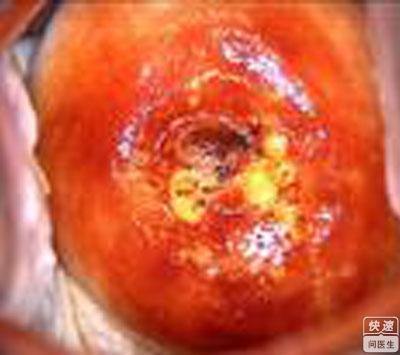

宫颈癌图片高清

宫颈癌的出血图片

宫颈癌晚期整个宫颈图

宫颈癌的早期出血图片

宫颈癌晚期症状图片